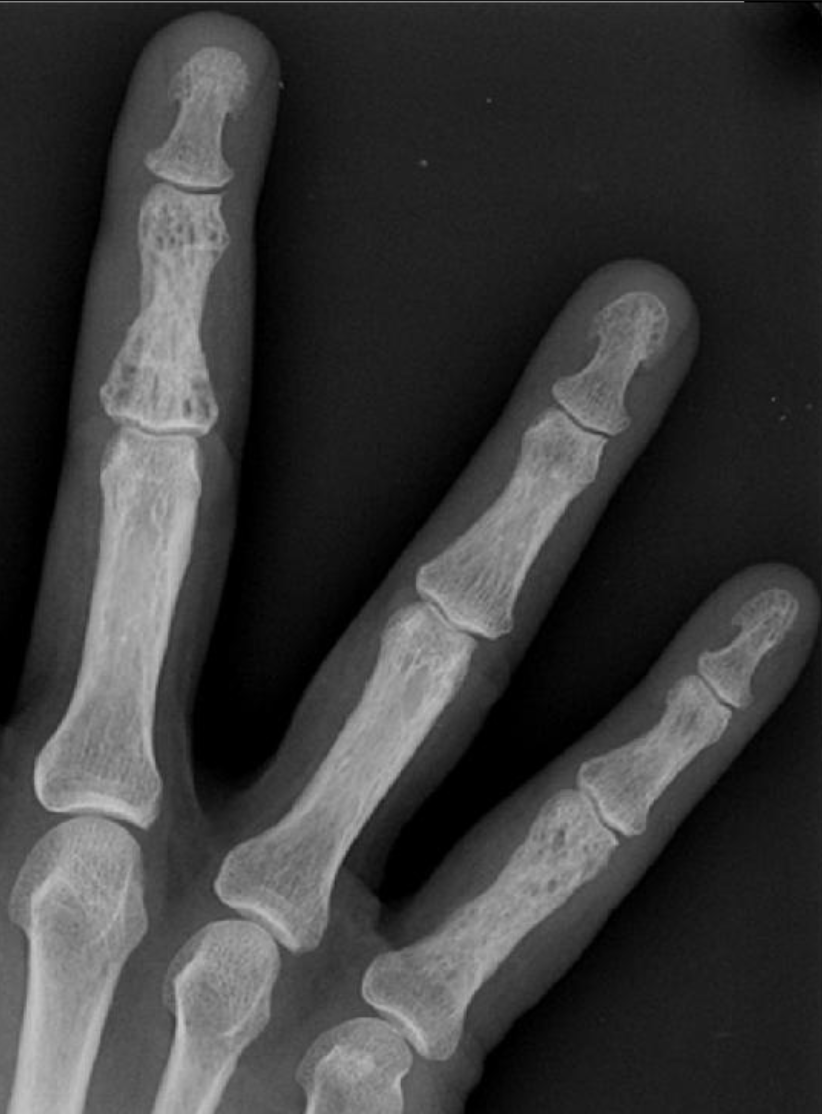

Sarcoidosis

• Lace-like/honeycomb appearance of the fingers

Bizarre Parosteal Osteochondromatous Proliferation (Nora lesion)

• Basically localized hypertrophy of the cortex, usually in hands and feet

• Does not typically affect medulla

• Benign, no treatment

• Very similar to osteochondromas

• Note: OC will connect with medulla and are typically oriented away from the nearby physis, both of which are not seen in Nora lesions